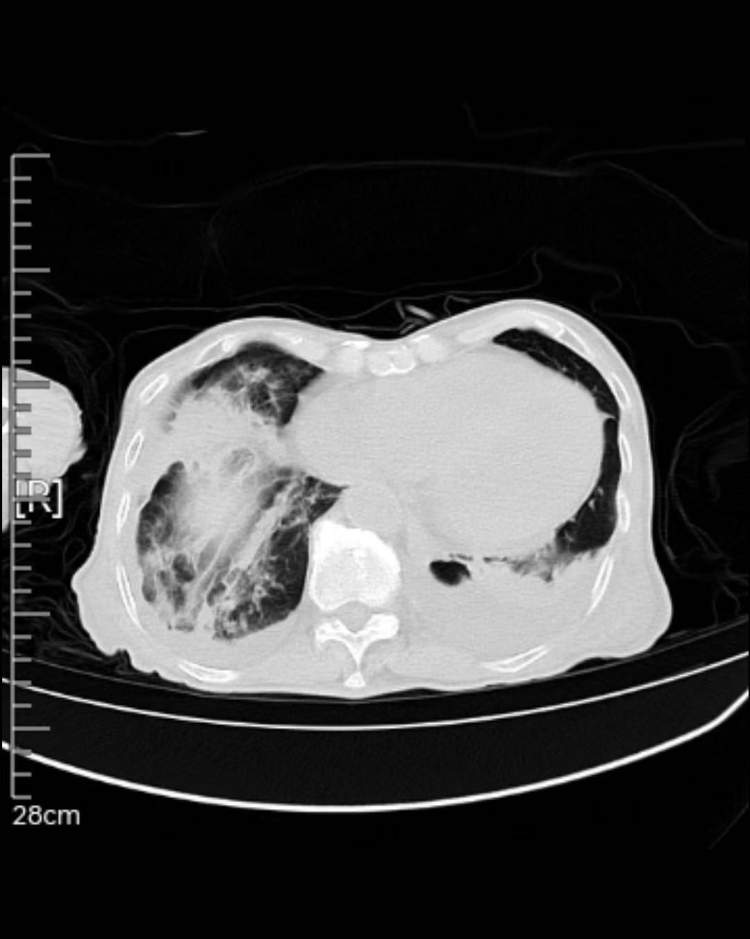

张老伯来仁济医院就诊后,被骨关节外科主任医师林瑞新收治入院,检查后发现,张老伯有新发的大面积脑梗、严重肺部感染、两侧胸腔积液、心功能不全以及低蛋白血症,BNP高达878.0pg/mL,白蛋白低至27.2g/L。并且张老伯的精神状态也不佳,总是昏昏沉沉、打不起精神。